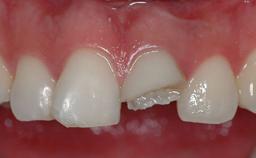

Missing Maxillary Central Incisor, Single Implant Replacement with Adjacent Tooth Restoration

The patient presented with a failing tooth-supported fixed dental prosthesis with cantilever extension replacing the right maxillary central incisor. His chief presenting complaint was poor esthetics, in particular the dark discolored margin around the abutment tooth, the maxillary left central incisor. He reported a history of trauma at a young age, which necessitated the replacement of his maxillary right central incisor as well as root canal therapy of the adjacent left central incisor. The existing prosthesis had been in situ for over 20 years. The initial periapical radiograph displayed good proximal bone levels at the adjacent teeth and a wide incisive canal, which was a concern. The left central incisor presented a very wide root canal treatment with compromised radicular dentin thickness, which was a consideration in the decision between a new tooth-supported fixed dental prosthesis vs. an implant-supported prosthesis. After a lengthy discussion on the risks and benefits of both treatment options, the patient decided on a single-tooth implant replacement.